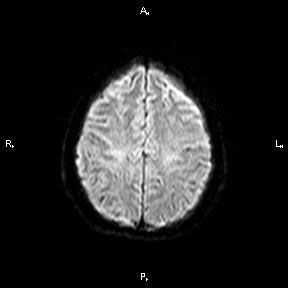

Магнитно-резонансная томография ( МРТ ) - наиболее предпочтительный метод в определении локализации, а главное - в оценке стадии развития ишемического процесса. В острую фазу наибольшую информацию несут диффузионно-взвешенные изображения (сокращенно: ДВИ) - изображения, полученные с помощью специализированной импульсной последовательности, предусмотренной в МР-томографах экспертного класса, которую мы применяем при исследовании всех без исключения пациентов.

При использовании ДВИ можно увидеть минимальное изменение диффузии (скорости движения) жидкости в мозговой ткани на молекулярном уровне, что является первым признаком ишемического повреждения головного мозга. Кроме того, при исследовании головного мозга у пациента с подозрением на лакунарный инфаркт (как и во всех других случаях) мы применяем весь набор импульсных последовательностей, соответствующий международному стандарту, для выявления возможных сопутствующих изменений.

Пациентка 32 года. После посещения невролога обратилась в кабинет МРТ для исключения системного поражения центральной нервной системы с предварительным диагнозом "транзиторная ишемическая атака".

При сканировании головного мозга в нескольких режимах в кортикальных отделах левой теменной доли был обнаружен лакунарный инфаркт диаметром 7мм. Острый инфаркт хорошо виден на ДВИ (импульсная последовательность, доступная в томографах экспертного класса), но плохо виден в режиме с подавлением сигнала от свободной жидкости.

После проведенного лечения состояние пациентки улучшилось. На МР-томографии спустя 3 месяца заметна положительная динамика.